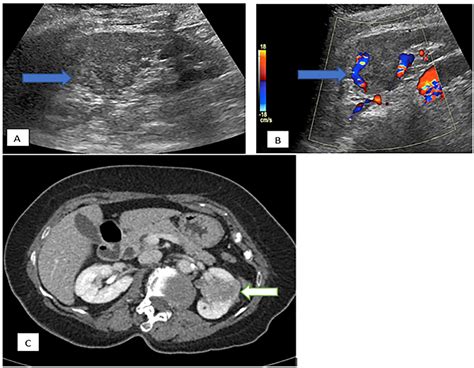

• hypertrophied column of bertin radiology

• prominent column of bertin kidney

• column of bertin ct

• hypertrophied column of bertin

• column of bertin hypertrophy

• column of bertin kidney